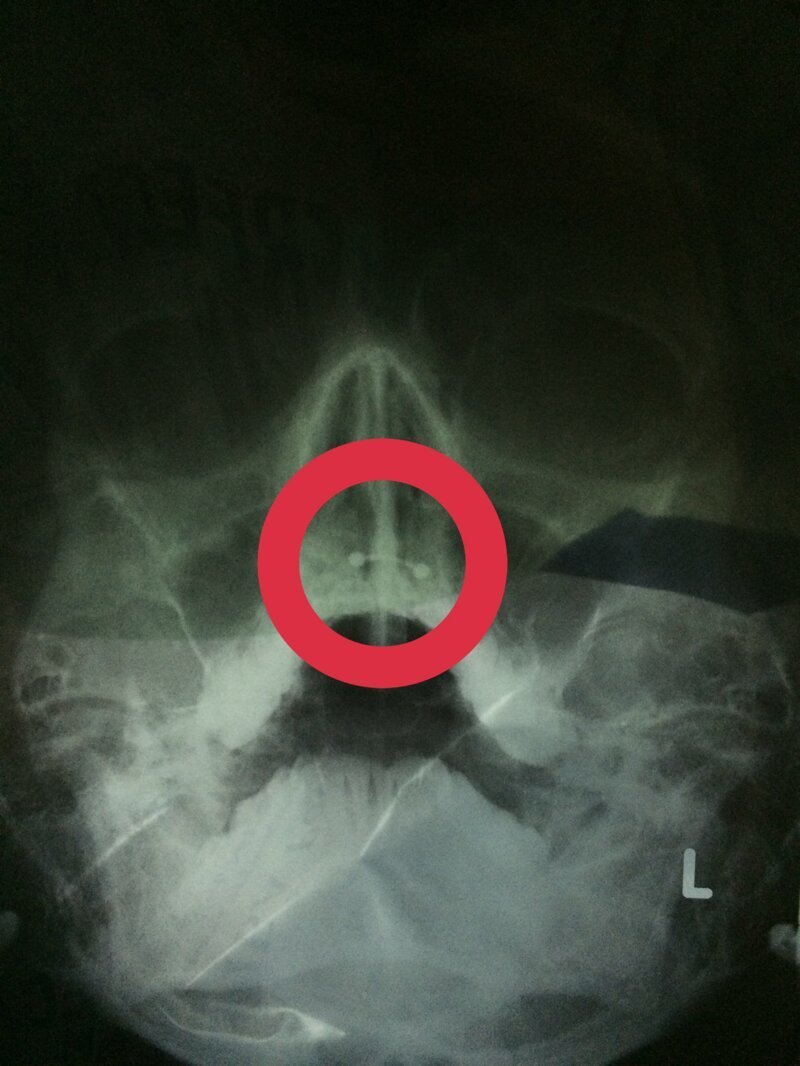

А это рентген с контрастированием сонных артерий. Выглядит жутковато только для непосвященных